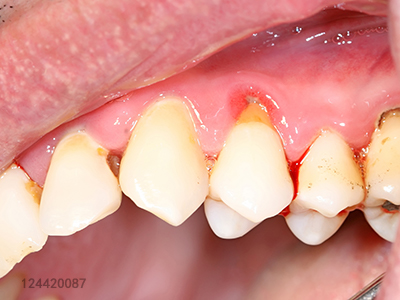

牙龈出血大部分是因为牙龈炎!健康的牙龈呈粉红色,质地坚韧。而发炎的牙龈会变成红色,浮肿疏松,血管浅漏,一碰便容易出血。

牙龈炎实际上是最轻微的牙周病,只需简单的治疗和护理,很快就能恢复健康。但如不重视,炎症将慢慢加剧,发展成牙周炎,长期以往将导致牙槽骨吸收、掉牙等严重后果。

如果牙龈炎反复出血、红肿,一直都得不到有效治疗,就会进一步发展,形成牙周病。此时会发现自己的牙缝变大,随着牙槽骨的吸收,牙龈开始萎缩,牙龈出血状况进一步加重,有时伴有牙龈充血溢脓。